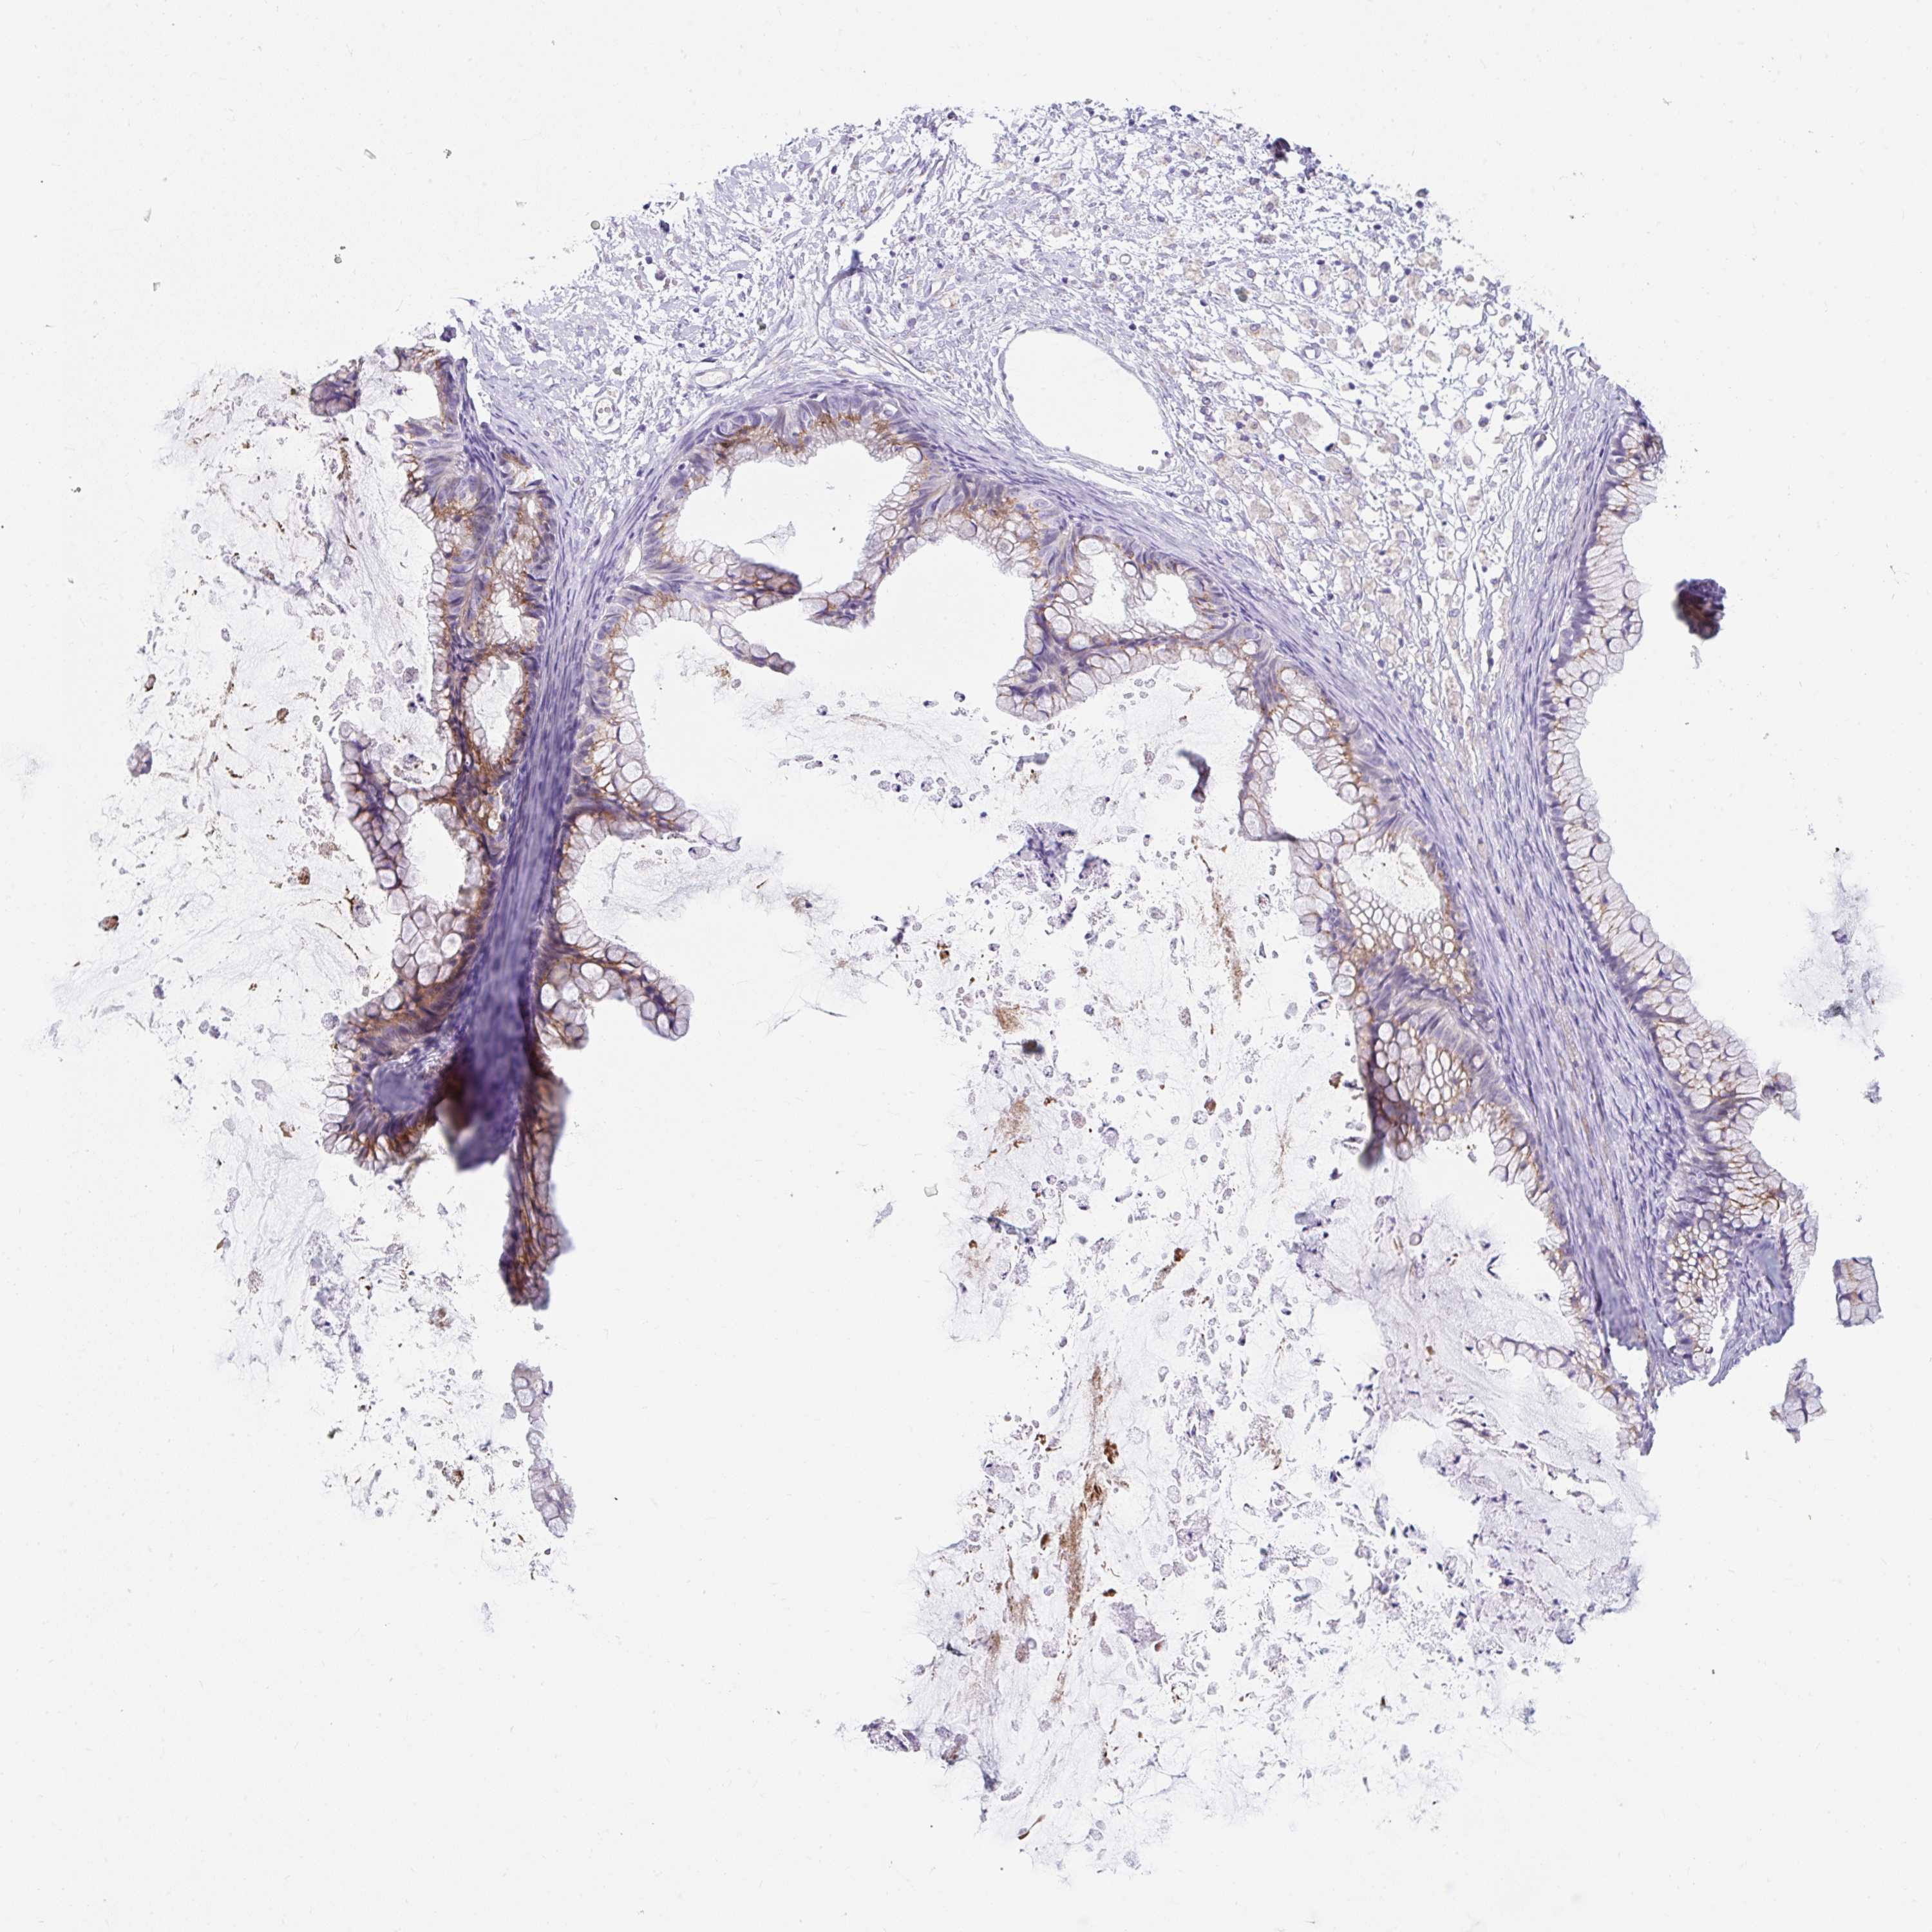

OVARIAN CANCER - Protein expressioni

A mouse-over function shows sample information and annotation data. Click on an image to view it in a full screen mode. Samples can be filtered based on level of antibody staining by selecting one or several of the following categories: high, medium, low and not detected. The assay and annotation is described here.

Note that samples used for immunohistochemistry by the Human Protein Atlas do not correspond to samples in the TCGA dataset.

Antibody stainingi

Antibody staining in the annotated cell types in the current human tissue is reported as not detected, low, medium, or high, based on conventional immunohistochemistry profiling in selected tissues. This score is based on the combination of the staining intensity and fraction of stained cells.

Each image is clickable and will lead to virtual microscopy that enables deeper exploration of all samples and also displays staining intensity scores, fraction scores and subcellular localization as well as patient and tissue information for each sample.

Antibody HPA051808

Cystadenocarcinoma, serous, NOS

Carcinoma, NOS

Cystadenocarcinoma, mucinous, NOS

Carcinoma, endometroid